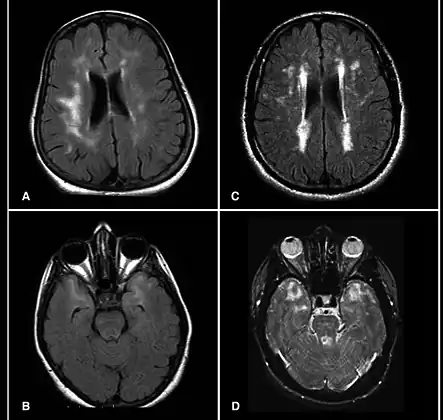

CADASIL is an inherited disorder caused by mutations in the NOTCH3 gene located on chromosome 19.[19] NOTCH3 codes for a transmembrane protein whose function is not well-known. However, the mutation causes accumulation of this protein within small to medium-sized blood vessels.[19] This disease often presents in early adulthood with migraines, stroke, mood disturbances, and cognitive deterioration. MRI shows white matter changes in the brain and also signs of repeated strokes. The diagnosis can be confirmed by gene testing.[20]

MRI demonstrating white matter changes in the brain of patients with CADASIL